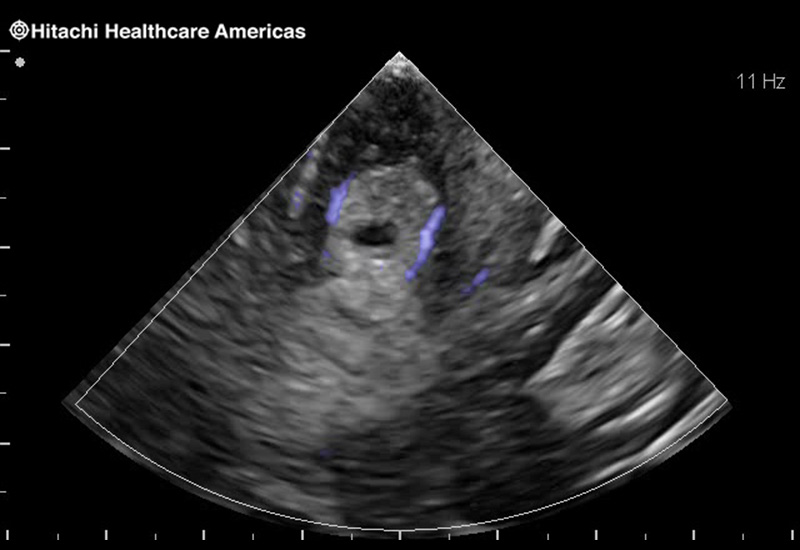

Superior guidance for all applications

Fujifilm Healthcare Americas is committed to designing tools that help surgeons navigate inside the human body and provide the necessary information to immediately make critical surgical decisions.

Fujifilm Healthcare's dedication to Surgeons provides outstanding ultrasound technology, professional support and the specialized tools necessary to best perform comprehensive real-time ultrasound imaging in Breast Surgery, General Surgery, Laparoscopic Surgery, Neurosurgery, Robotic Surgery and Surgical Oncology.

Recognized for our outstanding image quality, outstanding system reliability and intuitive use of cutting edge technology, Fujifilm Healthcare remains the standard in the field of Surgery.

Recognized for our outstanding image quality, outstanding system reliability and intuitive use of cutting edge technology, Fujifilm Healthcare remains the standard in the field of Surgery.